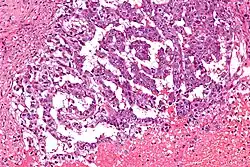

![]() Komórki pęcherzyka żółtkowego w obrazie mikroskopowym nowotworu zarodkowego jądra | |

W obrazie mikroskopowym typowe jest tworzenie struktur torbielowatych, przypominających budową zatokę żółtkową, złożonych z płaskich lub jajowatych komórek uwypuklających się do ich światła. Występują także ciałka Schillera-Duvala, złożone z małych okrągłych komórek skupiających się wokół drobnych naczyń krwionośnych. Charakterystyczną cechą guzów pęcherzyka żółtkowego jest produkcja α-fetoproteiny.